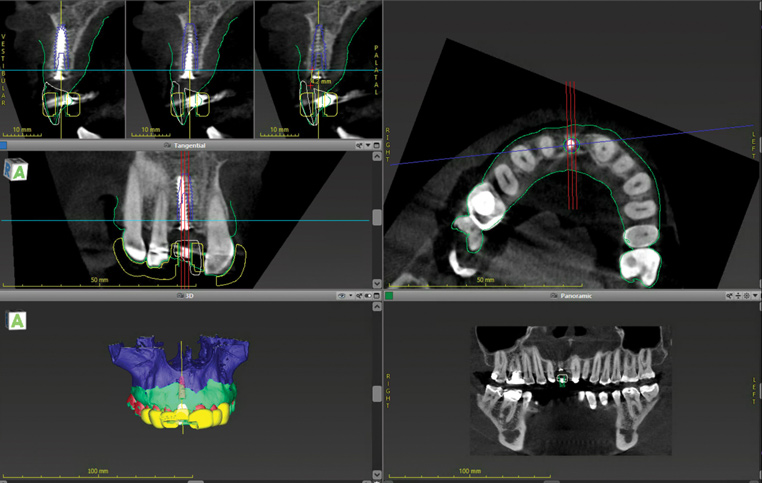

(7.) Pretreatment CBCT scan.

Figure 7

(14.) Three-dimensional implant treatment planning.

Figure 14

When the patient returned 4 months after the initial procedure for reevaluation, she underwent supportive periodontal therapy and was provided with detailed oral hygiene instructions (Figure 13). An intraoral scan and a postoperative CBCT scan were taken to evaluate both the horizontal and vertical hard- and soft-tissue gain. Next, implant planning software was used to merge the STL and DICOM data, which facilitated the creation of a digital wax-up (Figure 14).

The digital wax up allowed the implant position to be planned based on the ideal prosthetic position of the final restoration (Figure 14). The planned implant position adhered to the aforementioned guidelines for ideal implant placement regarding the buccal, interproximal, and apical bone, and its platform would be located 4-mm apical to the planned restorative margin. In the coronal plane, the implant was centered with the gingival zenith in a position that was located approximately 1-mm distal to the midline of the edentulous space. Following implant planning, a tooth-supported surgical guide was designed and then 3D-printed to facilitate fully guided surgical implant placement.